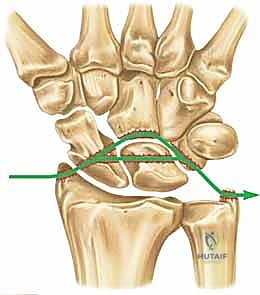

- Volar Extrinsic Ligaments: These are the prime stabilizers, arranged in a double-V configuration. This arrangement creates a relative weakness between the V's, famously known as the space of Poirier.

Figure 1A: Volar extrinsic carpal ligaments. Note the "space of Poirier" (), a critical area of capsular weakness.*